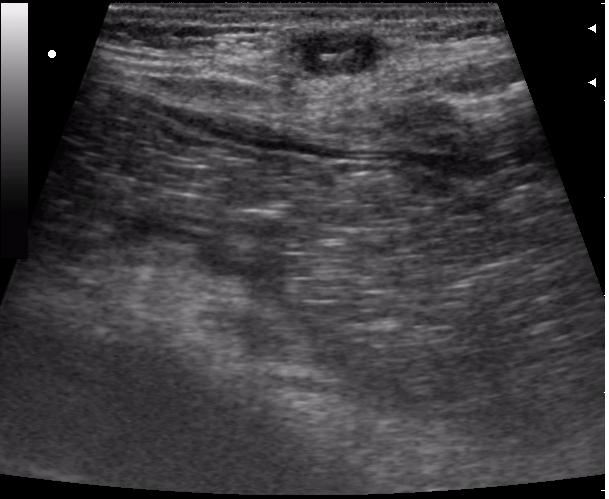

передняя брюшная стенка

просто прикольно выглядит, на коже изменений практически никаких. пациент сам по-себе с приколами (после операции б-нь Гиршпрунга, оперировали не у нас) показать?

Здесь в перспективе возможен лигатурный свищ.

хм... 3 года после операции прошло

Ну, как я и думал, более полугода.

Лигатура с изменениями окружающих тканей (стрелка)